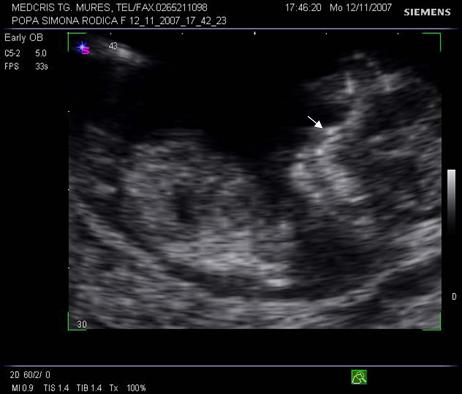

Fig. nr.129 Masurarea pliului nuchal la o marire corespunzatoare